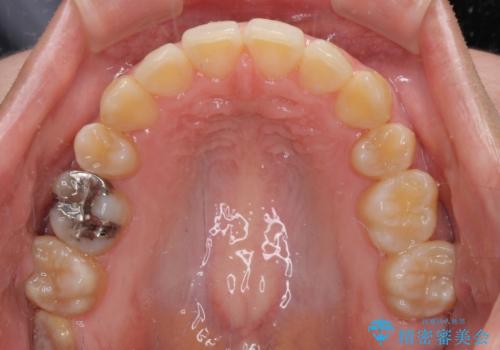

八重歯の抜歯矯正 補助装置を用いたインビザライン矯正

- 下の前歯のデコボコを気にして来院された患者様です。

来院当初、上顎の八重歯は気にしていらっしゃらなかったのですが、矯正治療をするのであれば、しっかりと治した方が良いと説明し、全顎矯正を行うこととしました。

八重歯の移動量が多く、インビザライン単体での治療は困難と判断し、補助装置により八重歯移動後にインビザラインを用いることとしました。